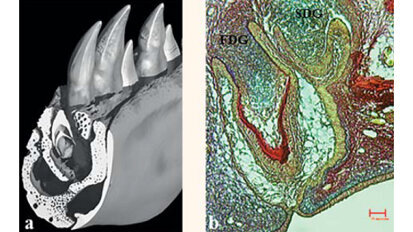

Regénération des dents grâce à une médicament contre Alzheimer

Londres, Royaume-Uni : Des scientifiques de l’institut dentaire du King’s College de Londres ont publié une nouvelle approche pour ...